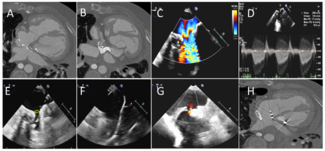

A 44-year-old man with history of D-transposition of the great arteries status post Mustard repair with pulmonary baffle obstruction was referred for further management. Cardiac computed tomography demonstrated calcific stenosis of the...